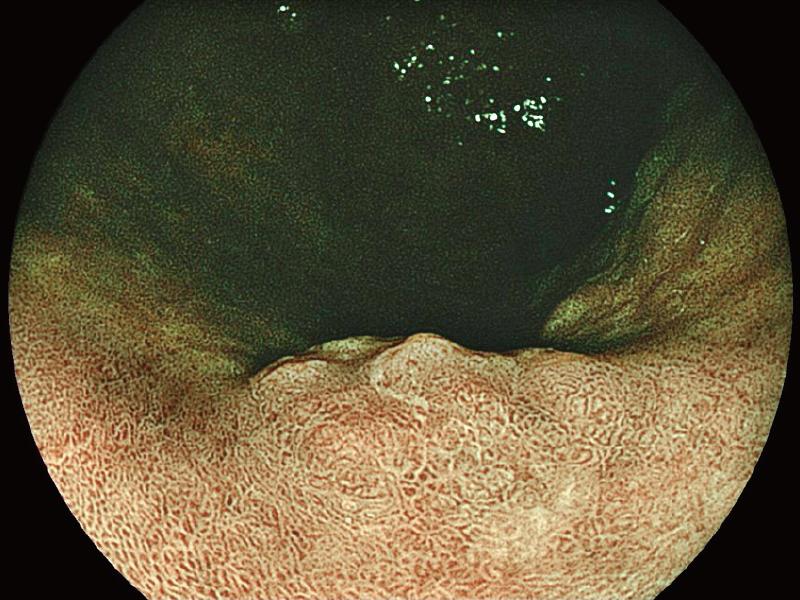

The 2mm close-up observation is expected to improve visibility during treatment.

*3

White Light Imaging

BLI (Blue Light Imaging)

*3 The images are not strictly close observation at 2 mm